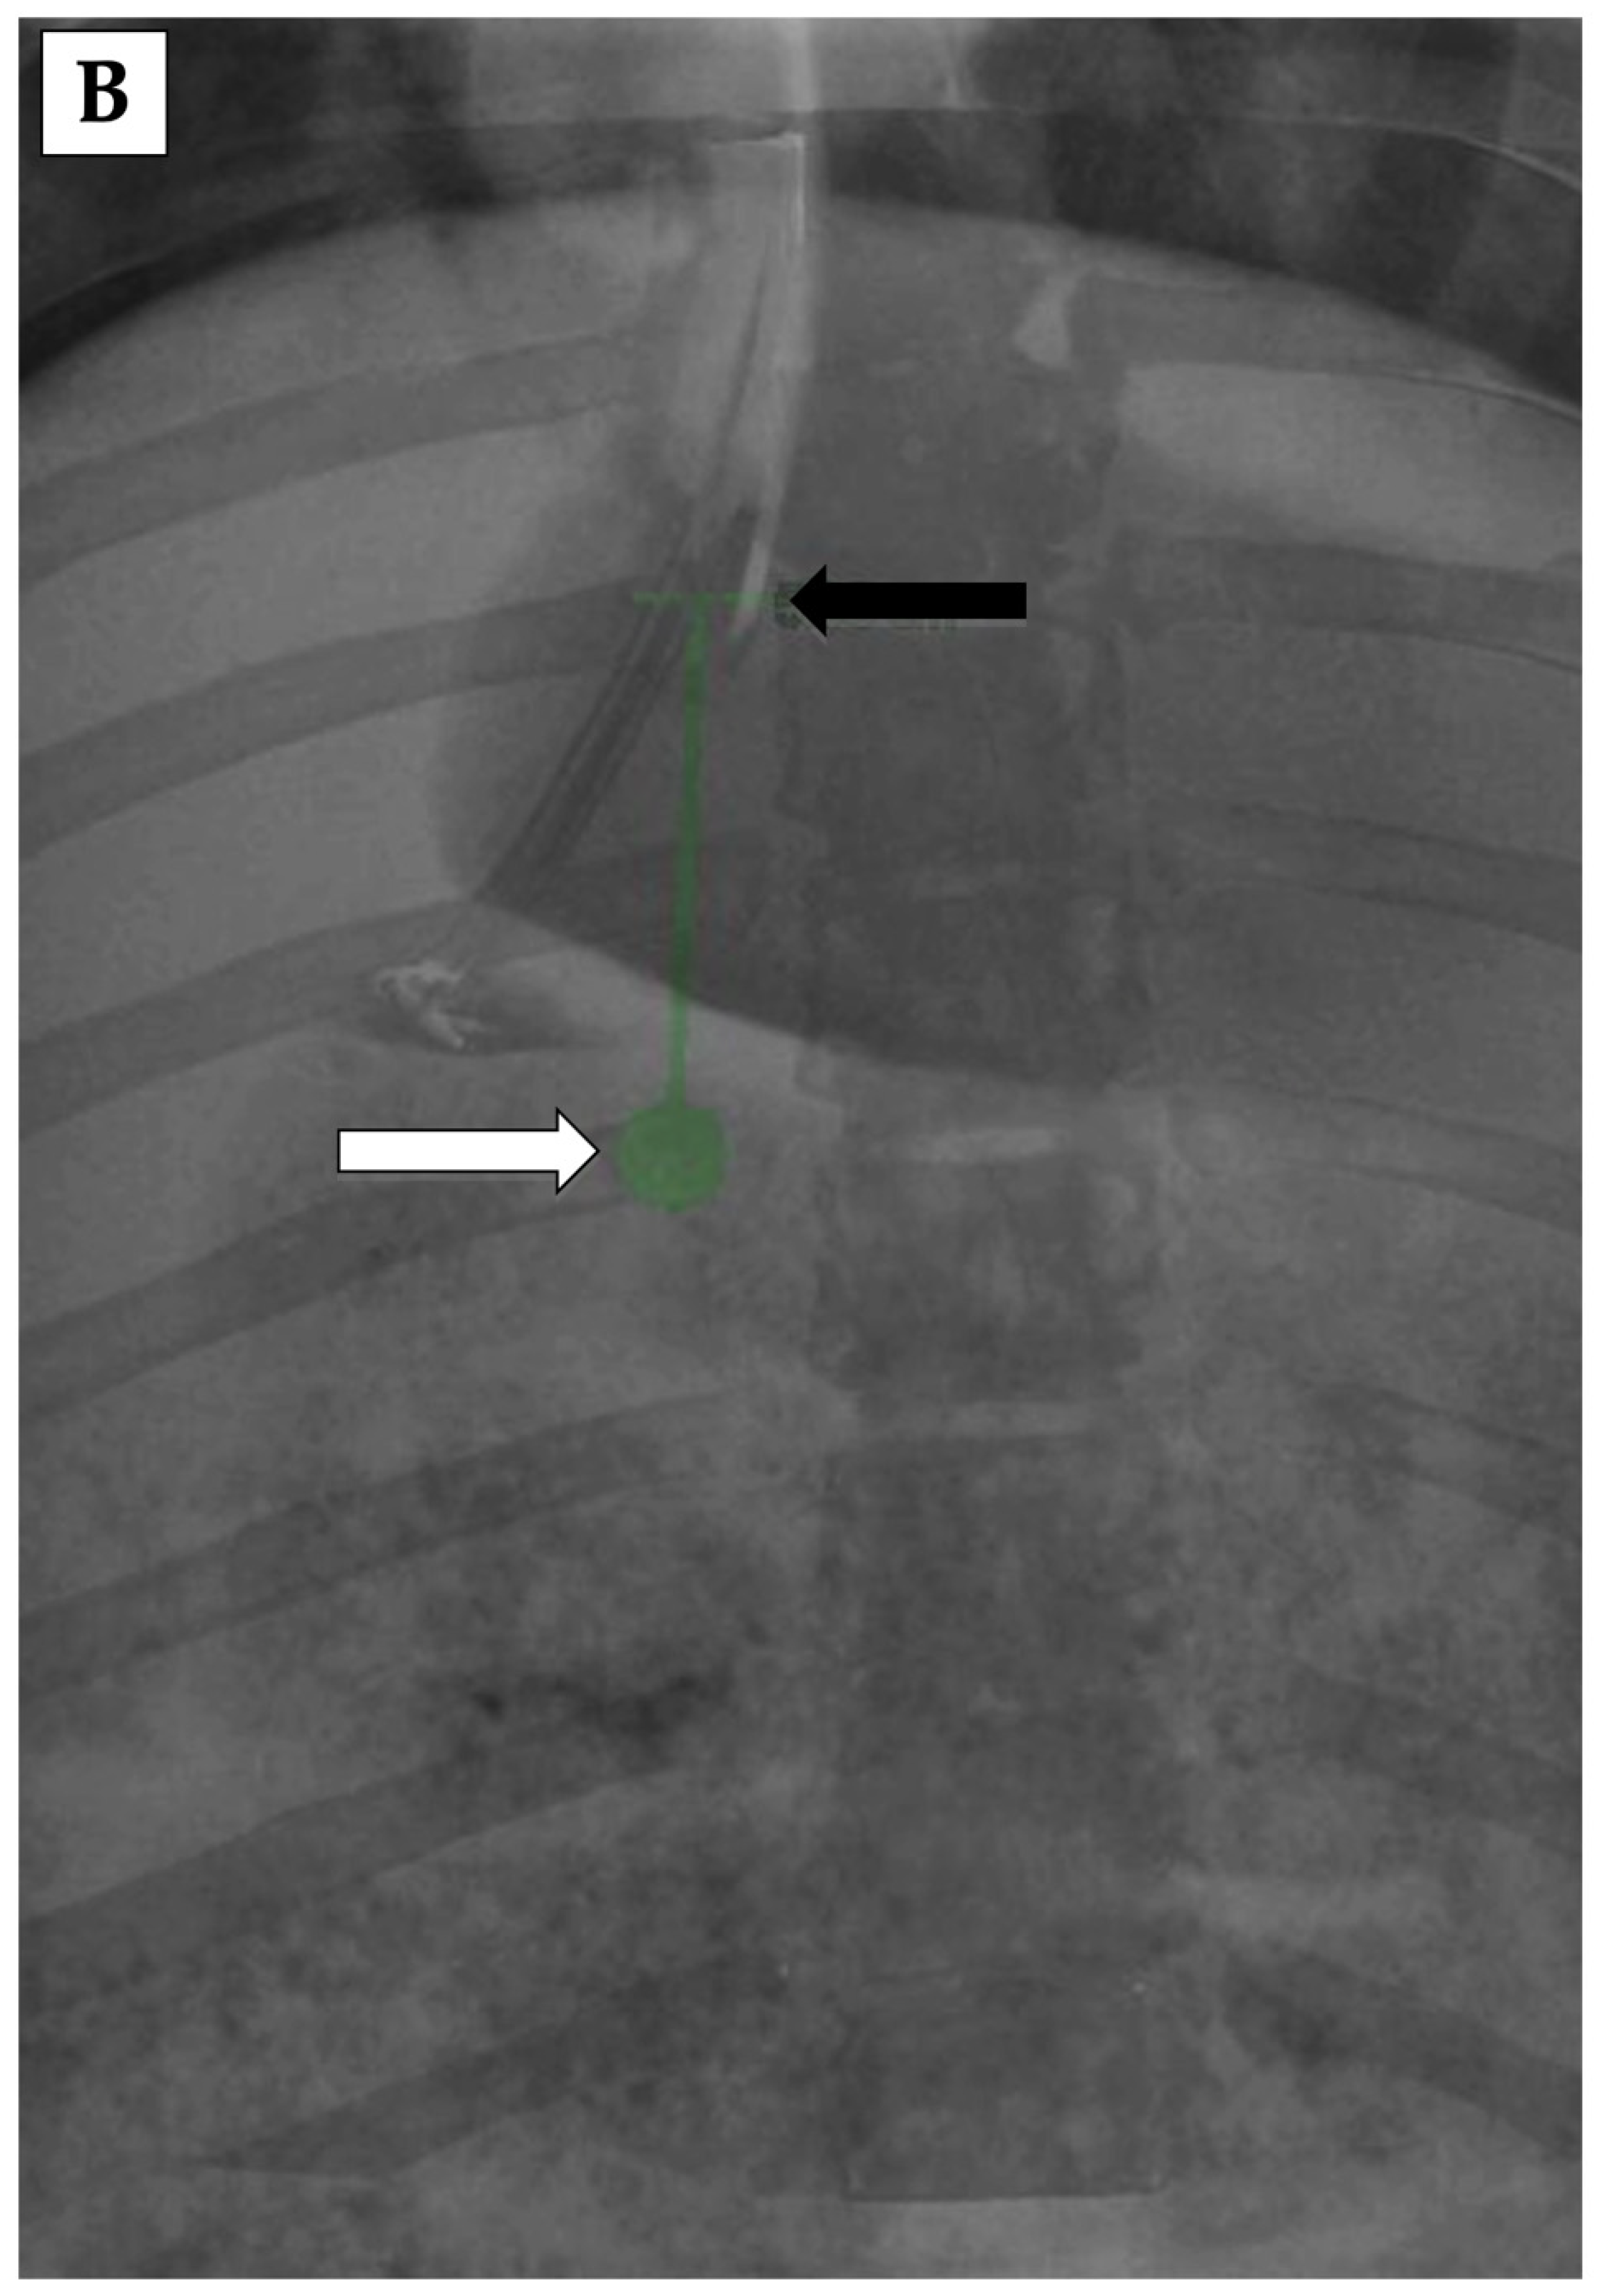

3.3. 3D Angiography-Guided TIPS Using CBCT/Angiography-Fused Images